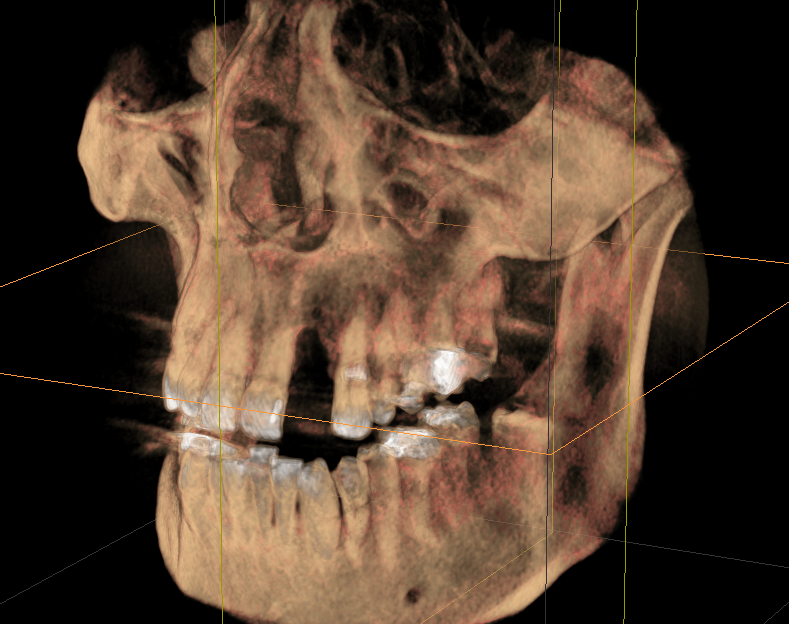

Bei nicht oder nicht vollständig durchgebrochenen Weisheitszähnen wird die darüber liegende Schleimhaut beiseite geschoben und der darüber liegende Knochen entfernt. Dann wird der Zahn mit einem Hebel entfernt. Ist dies aus anatomischen Gründen nicht im Ganzen möglich, wird das Durchtrennen des Zahnes notwendig. Das Trennen des Zahns ist obligat wenn die Platzverhältnisse keine andere Entfernungsmethode zulassen oder sich die Zahnwurzeln in unmittelbarer Nervnähe befinden. Die Wunde kann vernäht oder offen gelassen werden. Um Folgeschäden wie eine Taubheit der Unterlippe zu vermeiden kann präoperativ ein 3D DVT ( DIGITALES VOLUMENTOMOGRAMM ) zur Abklärung der Lagebeziehung von Wurzeln und Nerv sowie zur OP-Planung angefertigt werden.

Zu einer Wurzelspitzen-Entfernung wird Ihr Zahnarzt oder Kieferchirurg dann raten, wenn ein chronisch entzündlicher Prozess durch eine Wurzelbehandlung nicht behoben werden kann oder eine konventionelle Wurzelbehandlung nicht möglich ist. Auch wenn sich im Röntgenbild Veränderungen im Bereich der Wurzelspitze zeigen, die nicht eindeutig zuzuordnen sind, kann eine Wurzelspitzen-Resektion empfehlenswert sein. Um die Region der Wurzelspitzen genauer abzubilden ist es präoperativ möglich, durch ein 3D DVT (DIGITALES VOLUMENTOMOGRAMM) die Region dreidimensional abzubilden, um so eine bessere OP-Planung zu erhalten oder sich über die Frage der Erhaltungswürdigkeit des Zahns klar zu werden.

Solch ein Vorgehen erfordert allerdings auch eine möglichst exakte Diagnostik, die bei uns in der Regel dreidimensional mittels DVT erfolgt. So kann die Implantation vorher am Rechner dreidimensional simuliert werden, bevor sie am Patienten durchgeführt wird.